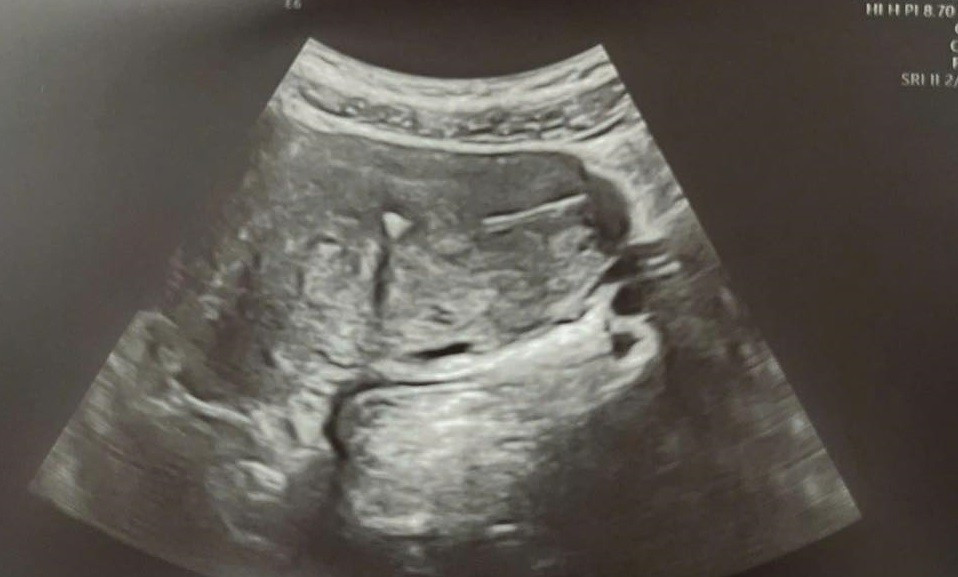

Vị trí của vòng tránh thai - Ảnh BVCC

Qua thăm khám, bác sĩ phát hiện vòng tránh thai đã cắm sâu vào lớp cơ tử cung, vị trí phức tạp và tiềm ẩn nguy cơ tổn thương nếu cố gắng tháo theo phương pháp thông thường. Chị được khoa Khám bệnh chỉ định siêu âm 3D phụ khoa để xác định chính xác vị trí vòng và đánh giá phương án xử trí phù hợp.

Với sự phối hợp của Khoa Chẩn đoán hình ảnh và Khoa Gây mê hồi sức, bác sĩ Hiếu chỉ định sử dụng siêu âm 3D phụ khoa để dựng hình buồng tử cung chi tiết, xác định chính xác vị trí vòng đang nằm vùi trong lớp cơ, còn một phần nhỏ nằm trong buồng tử cung nhưng sát góc, một phần khác thì thò ra ngoài tử cung vào bụng (nhìn thấy phúc mạc đội lên), từ đó xây dựng phương án can thiệp tối ưu.